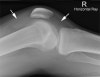

- Very Small

There appears to be a small amount of fluid in the supra-patella pouch (left arrow).

There is also fluid in Hoffa's Triangle (right arrow).